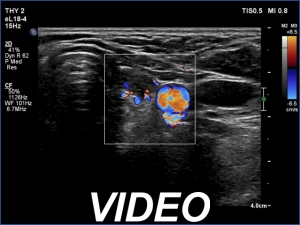

Clinical data: A 64-year-old woman came to a routine follow-up. She has been operated on a multinodular goiter for more than 20 years. A total thyroidectomy was performed. A recent thyroid ultrasound resulted in thyroiditis or recurrent nodule.

Ultrasonography. Great part of the lobes was composed of hypoechoic mass which showed irregular shape.

Overwhelming majority of the operated thyroids became hypoechoic.

This is one of the characteristic presentations of an operated thyroid, a lobe is partly hypoechoic partly echonormal.